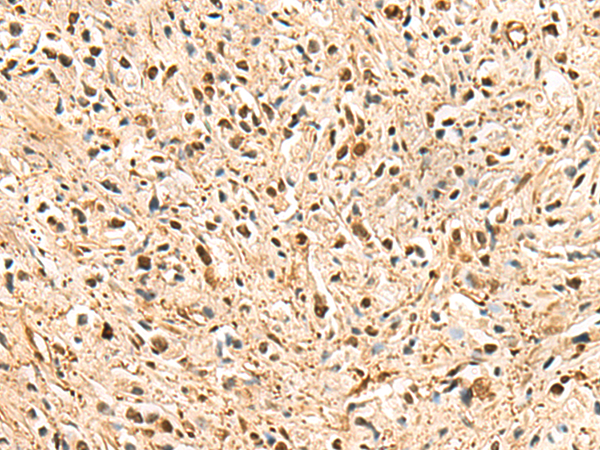

IHC positive control: |

Human ovarian cancer and Human thyroid cancer |

IHC Recommend dilution: |

40-200 |